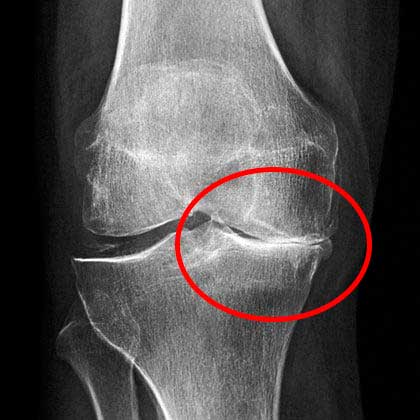

X-ray menunjukkan masalah serius dengan lutut saya

Berikut adalah kondisi lutut saya yang sehat saat ini